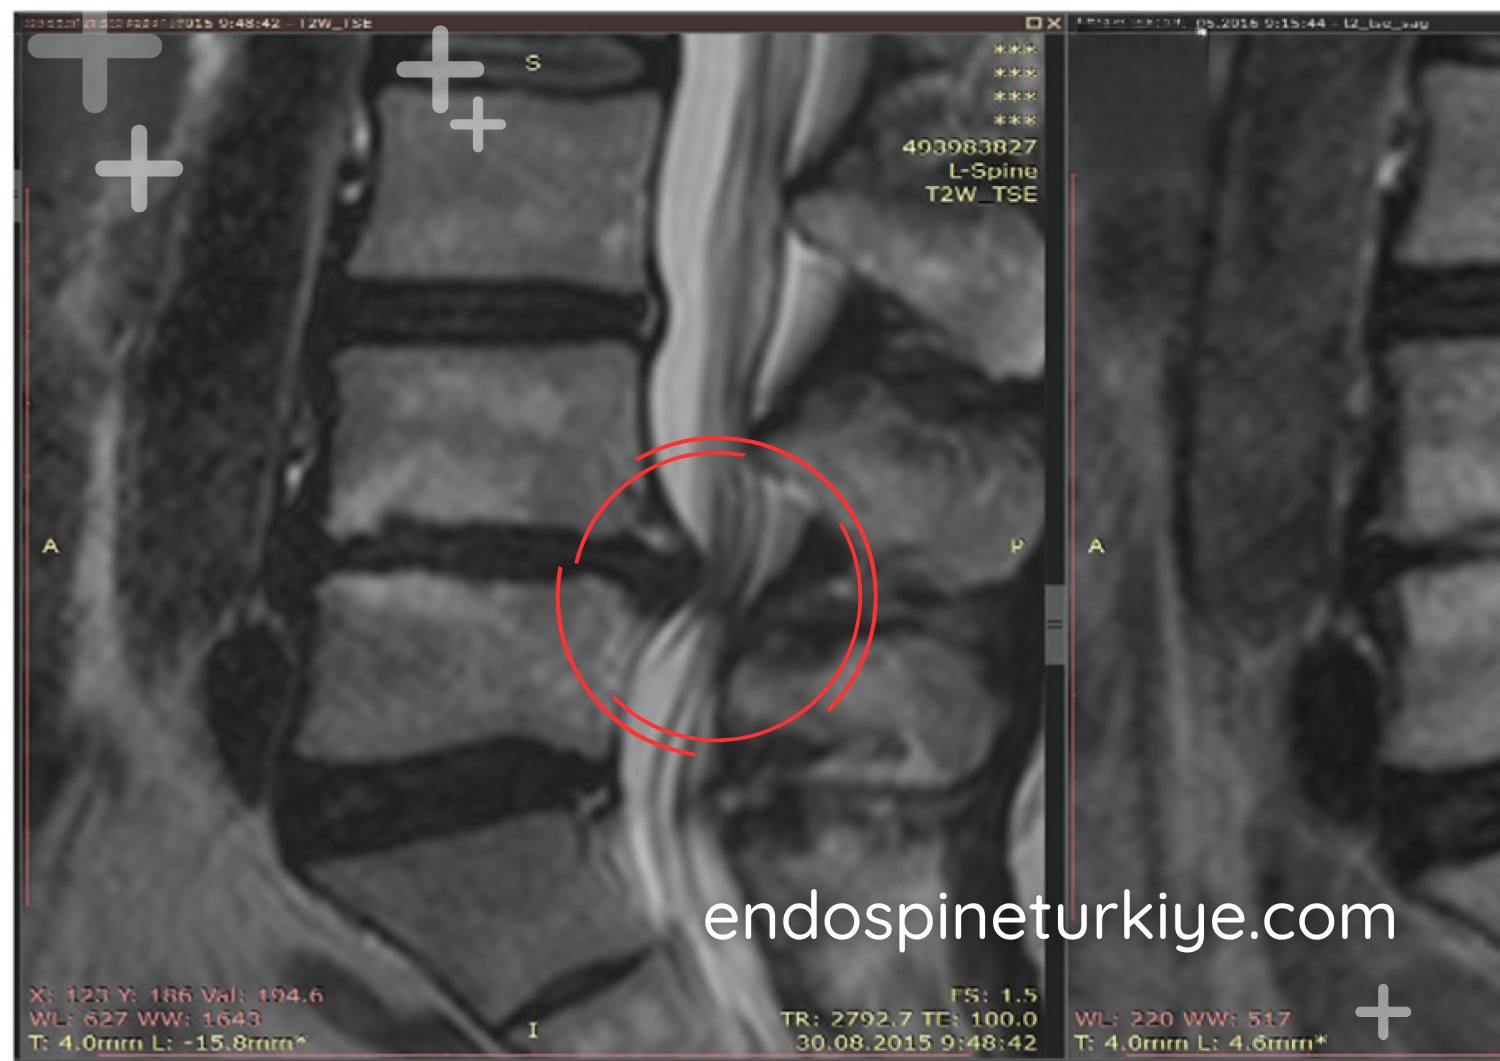

MR görüntülerinizi gönderin, Op. Dr. Rifat Saygın Altınağ tarafından ücretsiz ön değerlendirme yapılsın.